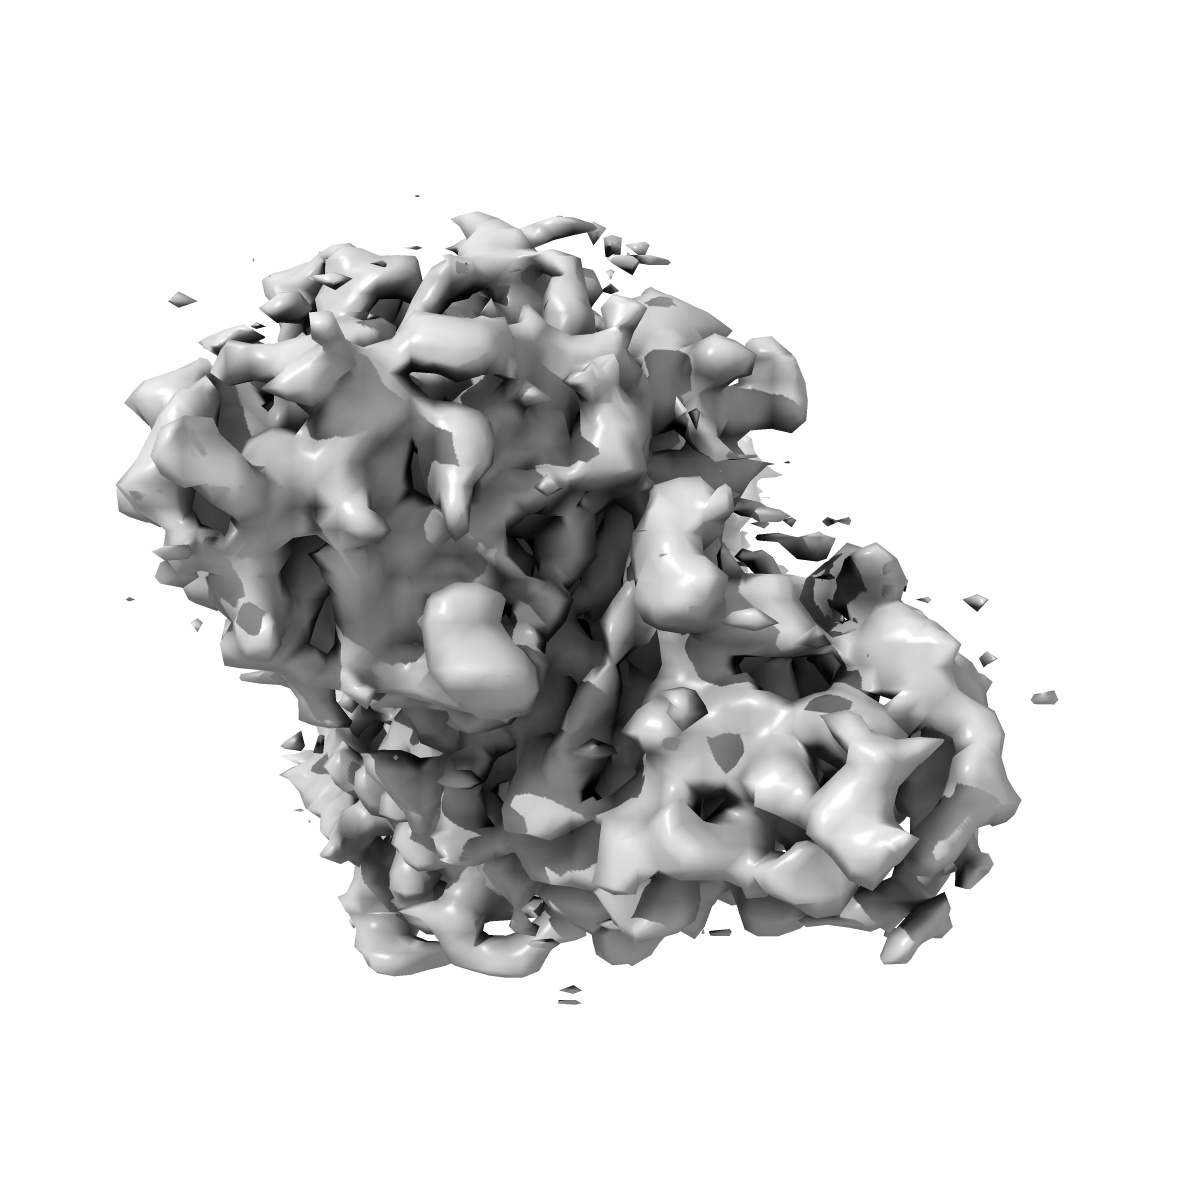

Cryo-EM structure of E. coli FimH lectin domain bound to Fabs 329-2 and 454-3

Single-particle3.12 Å

Sample: Ternary complex of E. coli FimH with Fabs 329-2 and 454-3

Structure-based design of an immunogenic, conformationally stabilized FimH antigen for a urinary tract infection vaccine.

(2025) PLoS Pathog , 21 , e1012325 - e1012325